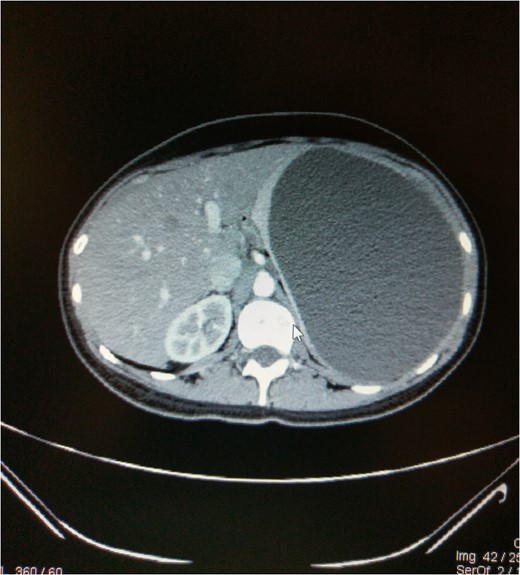

A 23-year-old female presented to the outpatient clinic of our hospital with complaints of abdominal fullness, early satiety, intermittent left upper quadrant abdominal pain and left flank pain for the last 3 months. No significant family history or history of trauma was described. Examination of the abdomen showed a non-tender enlarged mass in the left hypochondrium spanning upto the right iliac fossa. The report indicated a large space occupying lesion in the left upper quadrant of abdomen with probable origin being the spleen. A CT scan of abdomen and pelvis with IV contrast was advised for further evaluation which confirmed a 16.7 × 14.2 × 12.4 cm3 large splenic cyst on the upper outer pole with no intrinsic enhancement or internal septa, having a mass effect on the left kidney pushing it downwards and rotating it while putting a stretch on the left renal vessels (Figs 1 and 2). There was also a mass effect on the body and fundus of the stomach which explains the fullness and satiety by the patient. Serologic testing for Echinococcus was also performed and found to be negative.